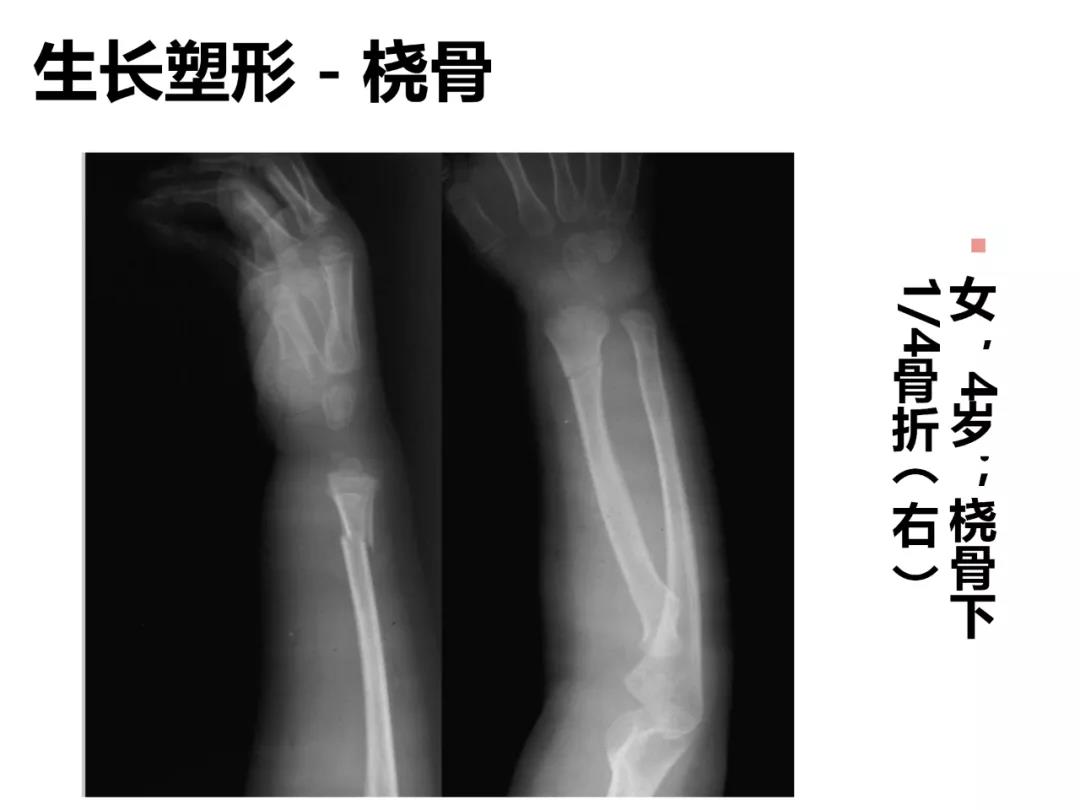

小儿骨科X线片汇总,临床读片宝典!